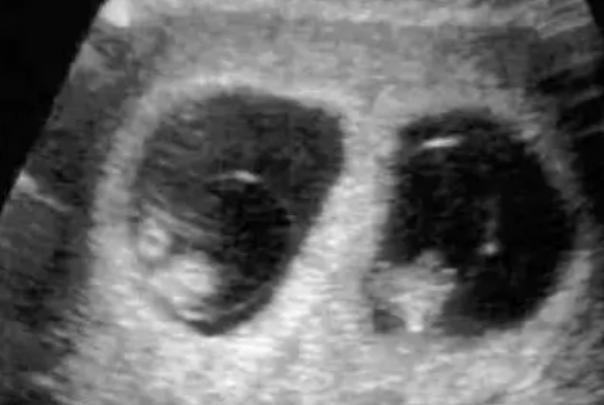

什么人容易怀单卵双胎,有家族史的同时生两个的概率高

单卵双胎,即由一个受精卵在早期发育过程中自然分裂形成两个独立胚胎所引发的双胞胎妊娠现象,其发生机制复杂且多为随机事件。与双卵双胎不同,单卵双胎不受遗传、人种或生育治疗的显著影响,其发生原因尚未被科学完全阐明,但大量临床观察与研究发现,某些特定人群或生理条件下,女性怀单卵双胎的概率可能存在微弱上升趋势。本文旨在梳理相关因素,为公众提供基于现有医学研究的科普解读。